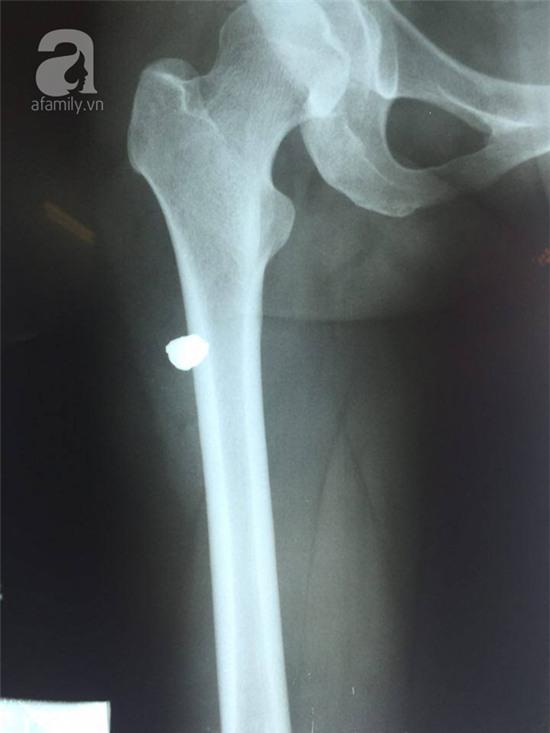

Liên quan đến vụ việc, một nạn nhân nữ ngồi sau xe máy, bị mảnh vỡ găm vào đùi và đã đến bệnh viện Quân Y 103 để chụp chiếu. Theo lời kể của nạn nhân, trước địa điểm xảy ra vụ nổ có một ngã tư đèn đỏ, rất may trước khi đèn đỏ kịp sáng thì người chồng chị cầm lái đã vượt qua. Khi đi qua vị trí nổ khoảng 150 m thì vụ nổ xảy ra và ngay sau đó người phụ nữ này thấy đau đùi phải và có máu chảy qua vết thương.

Các bác sĩ cho biết, kiểm tra qua phim chụp thì thấy có dị vật, lâm sàng không có tổn thương mạch hay thần kinh, vết thương nằm vị trí mặt sau ngoài tương ứng 1/3 trên đùi phải với kích thước khoảng 0,5 x 0,5 cm, bờ nham nhở, xung quay tấy đỏ, thành vết thương có dập nát.

Khảo sát sâu hơn nữa thấy ống vết thương đi từ trên xuống dưới, vào trong, trên đường đi có nhiều di vật kim khí cắm gắn lấm tấm. Sau phẫu thuật lấy dị vật thì phát hiện dị vật nằm trong cơ rộng ngoài là 1 mảnh kim loại và khả năng là mảnh gang có kích thước 1 x 0,5cm. Các bác sĩ đã phẫu thuật lấy dị vật, khâu dưới da.